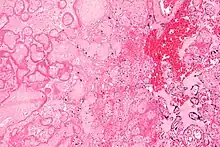

Micrograph of a placental infarct. H&E stain.

A placental infarction results from the interruption of blood supply to a part of the placenta, causing its cells to die.

Small placental infarcts, especially at the edge of the placental disc, are considered to be normal at term. Large placental infarcts are associated with vascular abnormalities, e.g. hypertrophic decidual vasculopathy, as seen in hypertension.[1] Very large infarcts lead to placental insufficiency and may result in fetal death.